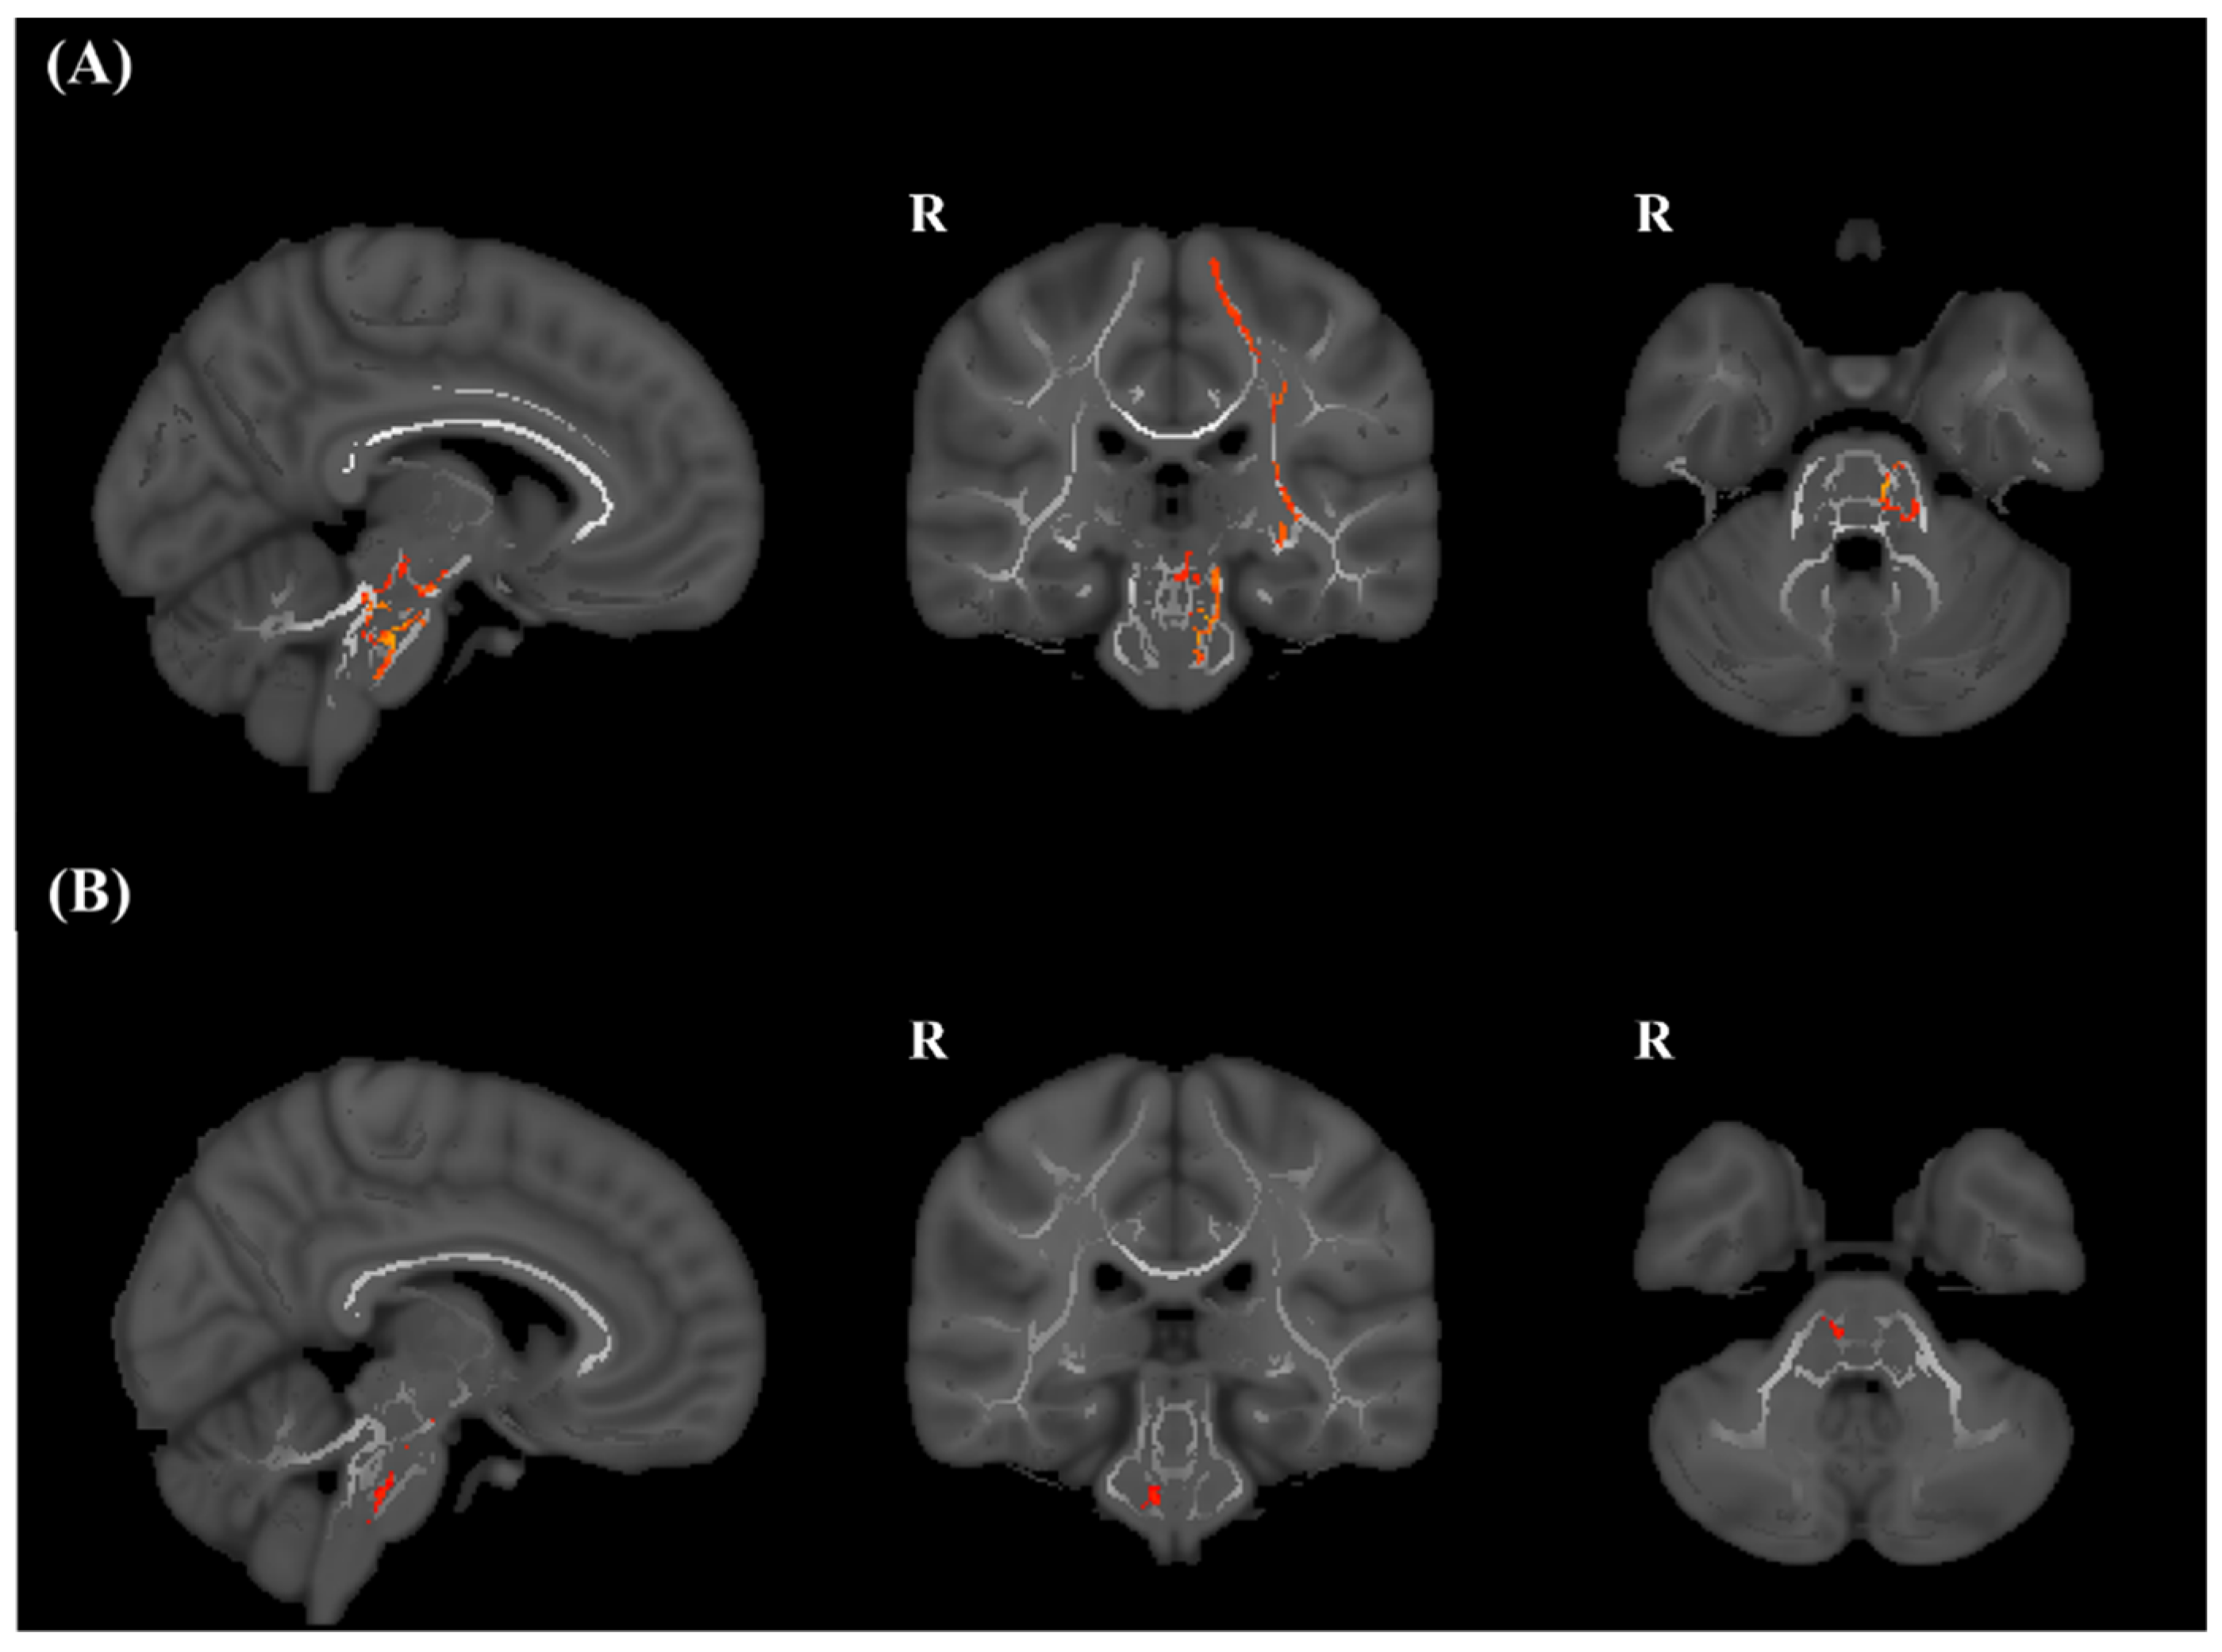

3.2. TBSS

3.3. ROI Analysis of FA of the CST in the Brain Stem